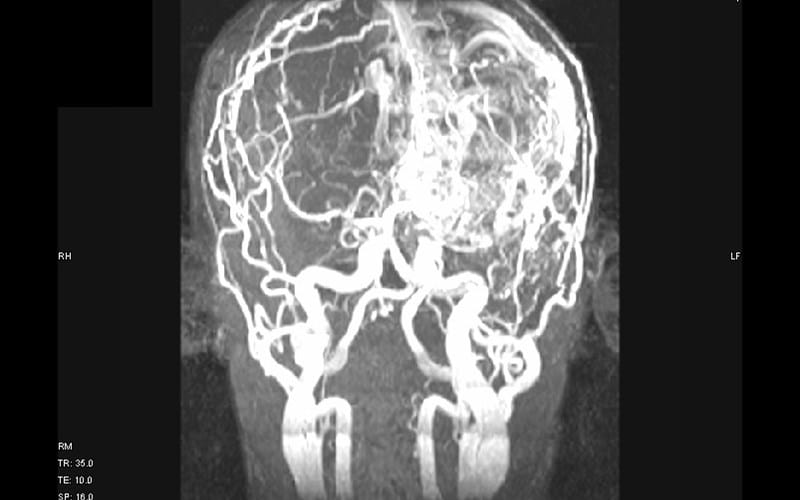

- церебральную ангиографию.

Компьютерная и магнитно-резонансная томография в случае патологии торпидного типа может оказаться неинформативной. Для подтверждения диагноза предпочтительна ангиография с использованием контрастного вещества. При разрыве весь комплекс диагностических мероприятий проводится экстренно, наибольшей информативностью при этом обладает МРТ.